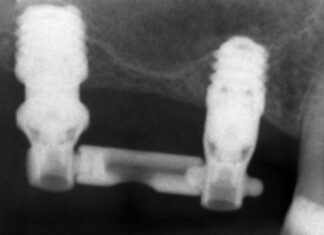

Ritrattamento canalare. Rimozione di 2 perni in fibra con tecnica ultrasonica

Il ritrattamento canalare è una procedura che si attua al fine di risolvere le problematiche endodontiche in essere e ha come scopo quello di...